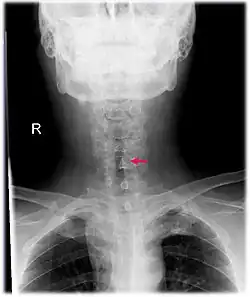

| Neck AP x-ray of patient with post-intubation subglottic stenosis, as shown by the narrowing in the tracheal lumen marked by the arrow. | |

CT scans and MRI (magnetic resonance imaging) can help in diagnosis. X-rays can determine the location and size of the narrowed airway portion. Optical coherence tomography (OCT) can help observe the progression of the injury. Esophageal pH monitoring can help detect any acid reflux, which can worsen the condition. A laryngoscopy or an endoscope can be inserted and used to see the vocal cords, airway, and esophagus/trachea. Spirometry is a useful way to measure respiratory function. People affected by subglottic stenosis have a FEV1 of over 10.[2]